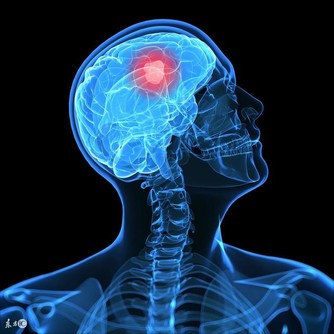

神經科學有個“認知儲備”概念。受過高等教育的人,因為額外的學習增加了大腦神經元之間的連接。當阿爾茨海默病開始阻斷這些連接時,大腦可以選擇備用路徑來補償,找回記憶。

研究證明,阿爾茨海默病患者大部分是散發,但是部分有家庭聚集的傾向。目前已經明確與阿爾茨海默病相關的基因有四對,分別為APP、PS1、PS2、APOE4基因。

如果家庭有好幾個,或者有好幾代人患病,就提倡做檢測。當然,攜帶高危基因,也不一定患病,還要看後天環境。